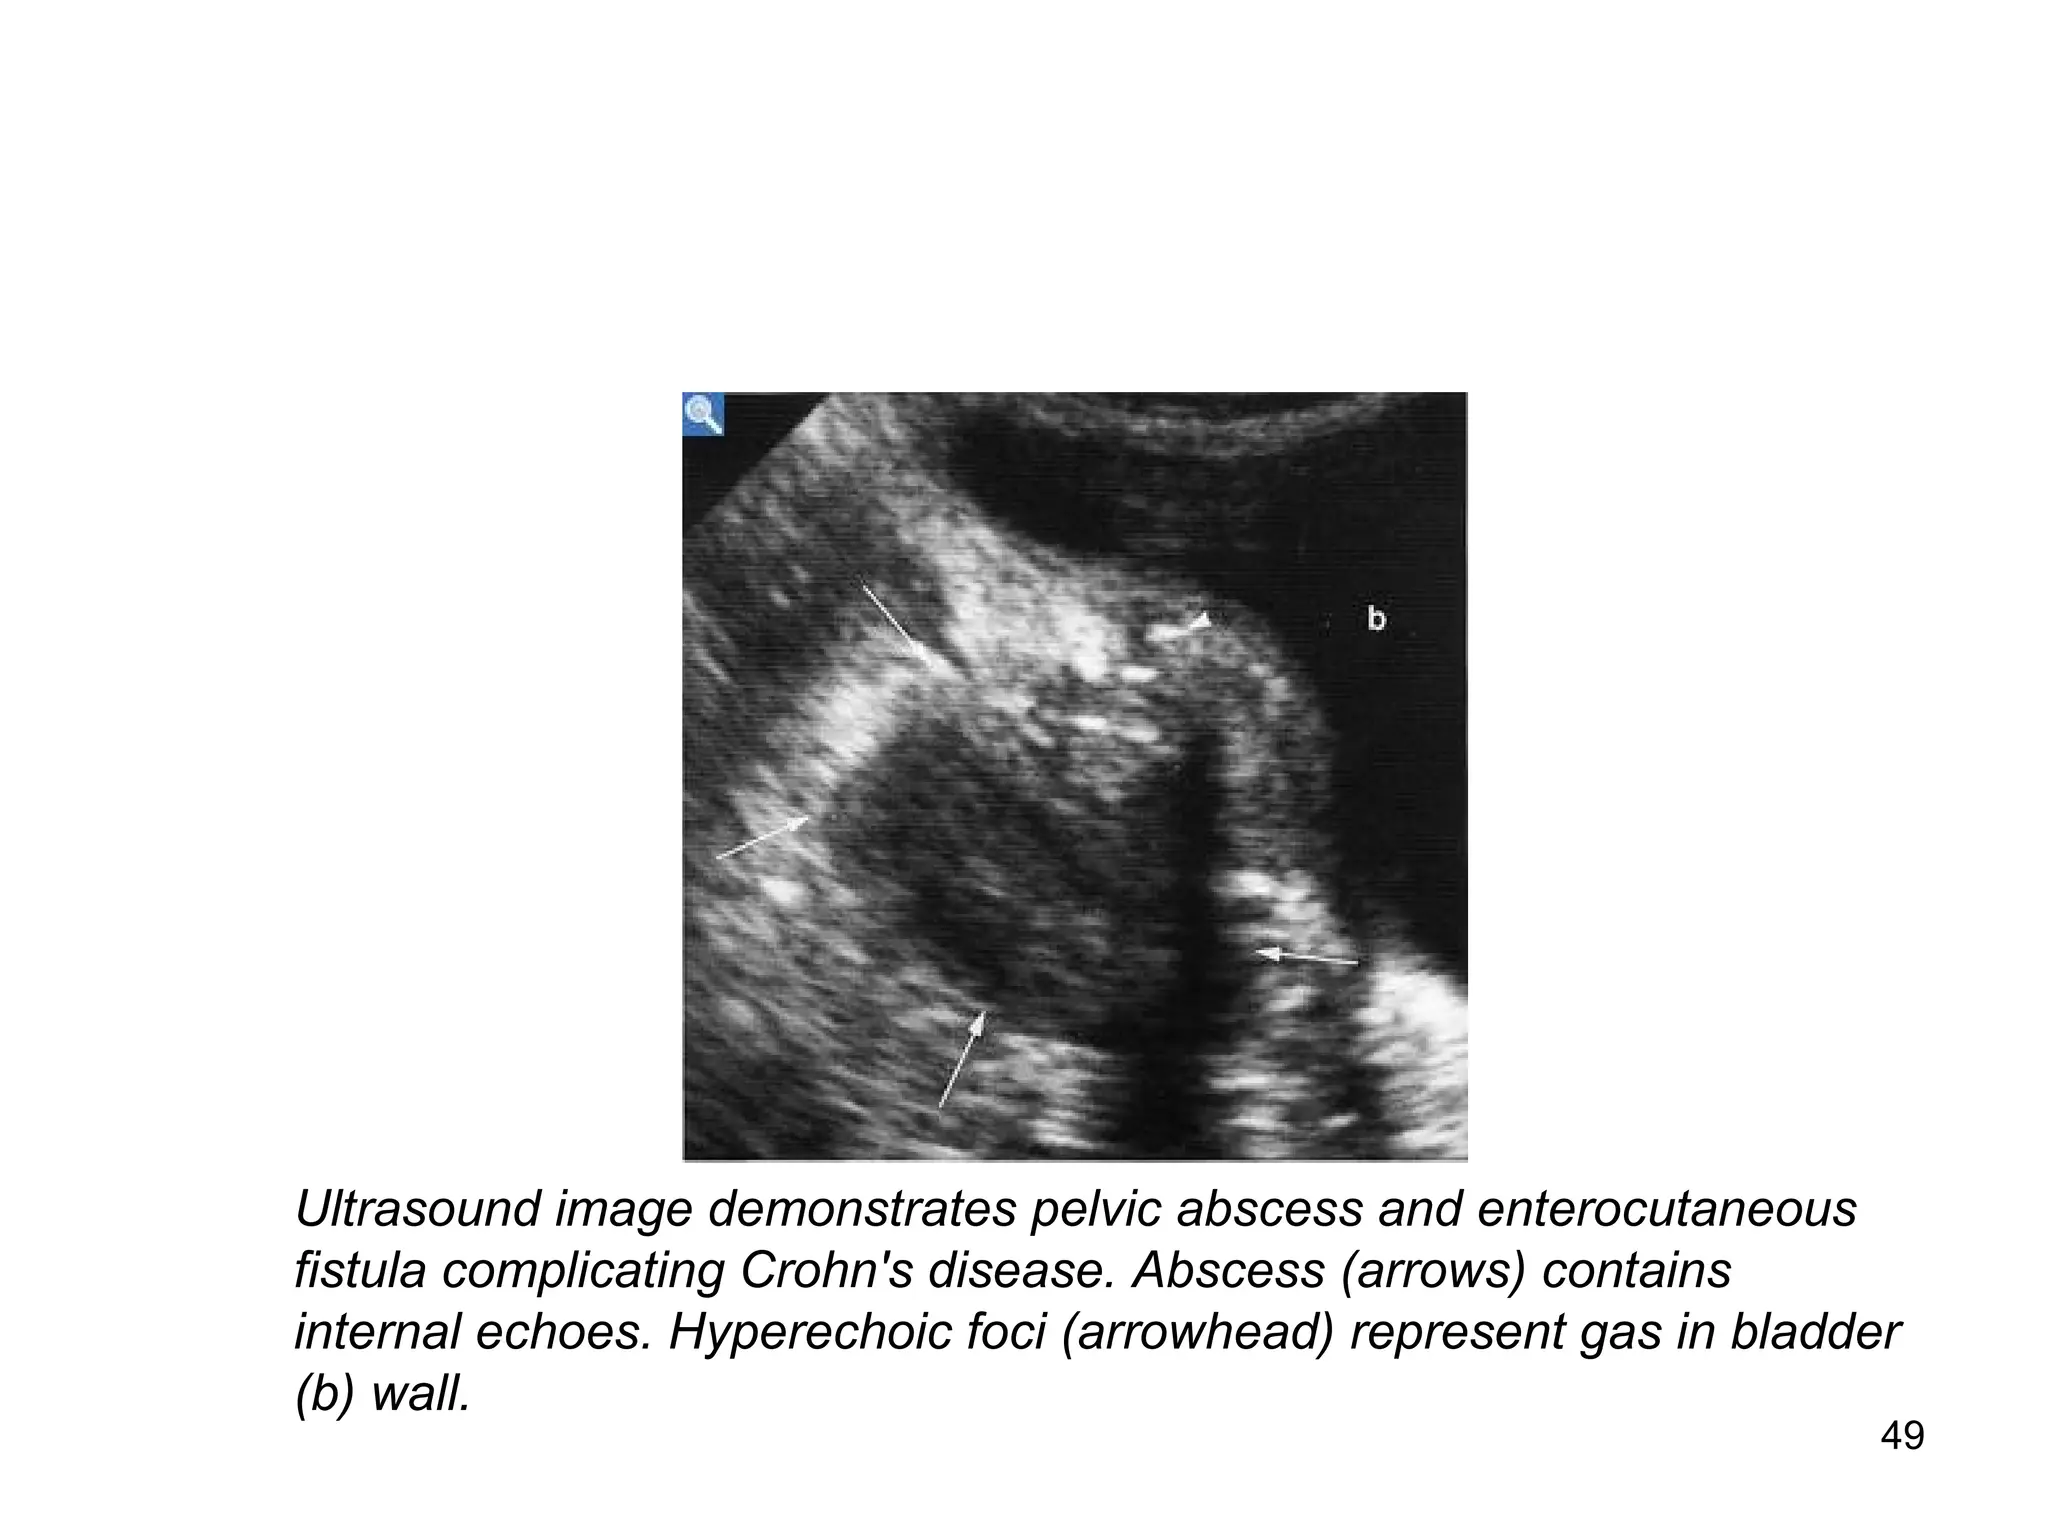

Ultrasound image demonstrates pelvic abscess and enterocutaneous

fistula complicating Crohn's disease. Abscess (arrows) contains

internal echoes. Hyperechoic foci (arrowhead) represent gas in bladder

(b) wall.

Same patient as previous slide. CT of pelvis

demonstrates thickened loop of ileum (small arrows),

fistula to bladder (arrowhead) and gas in bladder wall

(curved arrow) and in non-dependent aspect of bladder

itself. More cranial image better showed associated

abscess.